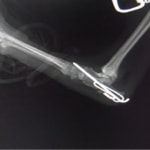

症例3:キルシュナーワイヤーのピンニングによる整復

ペルシャ猫 11ヶ月齢 雄

他院にて左大腿骨遠位の成長板骨折(salter-harrisⅠ型)が認められており、治療相談を目的として来院。当院にて、キルシュナーワイヤーを用いたピンニングにより骨折部位の整復を行いました。術後の経過は良好で、現在も経過観察中です。

術前レントゲン

術後レントゲン

機器

Arthrex社のターゲティングデバイスを用いてピンニングの位置を調整することで、確実な固定を行っています。当院ではこの手術器具以外にも、人の手術にも使用される様々な器具を導入し、手術精度を高め、また医療メーカーと新しい器具の開発、試作にも取り組んでおります。